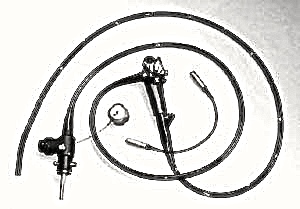

I en koloskopi undersøkes tykktarmen og tynntarmen fra innsiden. Man bruker et koloskop til dette. Et koloskop er en ca 2 meter lang bøyelig, fiberoptisk slange som føres inn i tarmen (nedenfra altså, i motsetning til et gastroskop som føres ned via svelget). Koloskopet fungerer etter samme prinsippet som et gastroskop. Man kan inspisere tarmens innside, overføre bilder til en tv-skjerm, og ta biopsier/vevsprøver. Undersøkelsen er aktuell feks ved mistanke om svulst eller betennelsestilstander som Crohns og Ulcerøs kolitt.